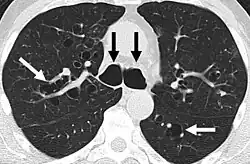

A chest X-ray is abnormal in most patients with bronchiectasis. Computed tomography is recommended to confirm the diagnosis and is also used to describe the distribution and grade the severity of the disease. Radiographic findings include airway dilation, bronchial wall thickening, and atelectasis.[65] Three types of bronchiectasis can be seen on CT scan, namely cylindrical, varicose, and cystic bronchiectasis.[66]

Bronchiectasis primarily in the middle lobe of the right lung. -

Bronchiectasis secondary to a large carcinoid tumor (not shown) that was completely obstructing the bronchus proximally. Dilation of the airways is present.